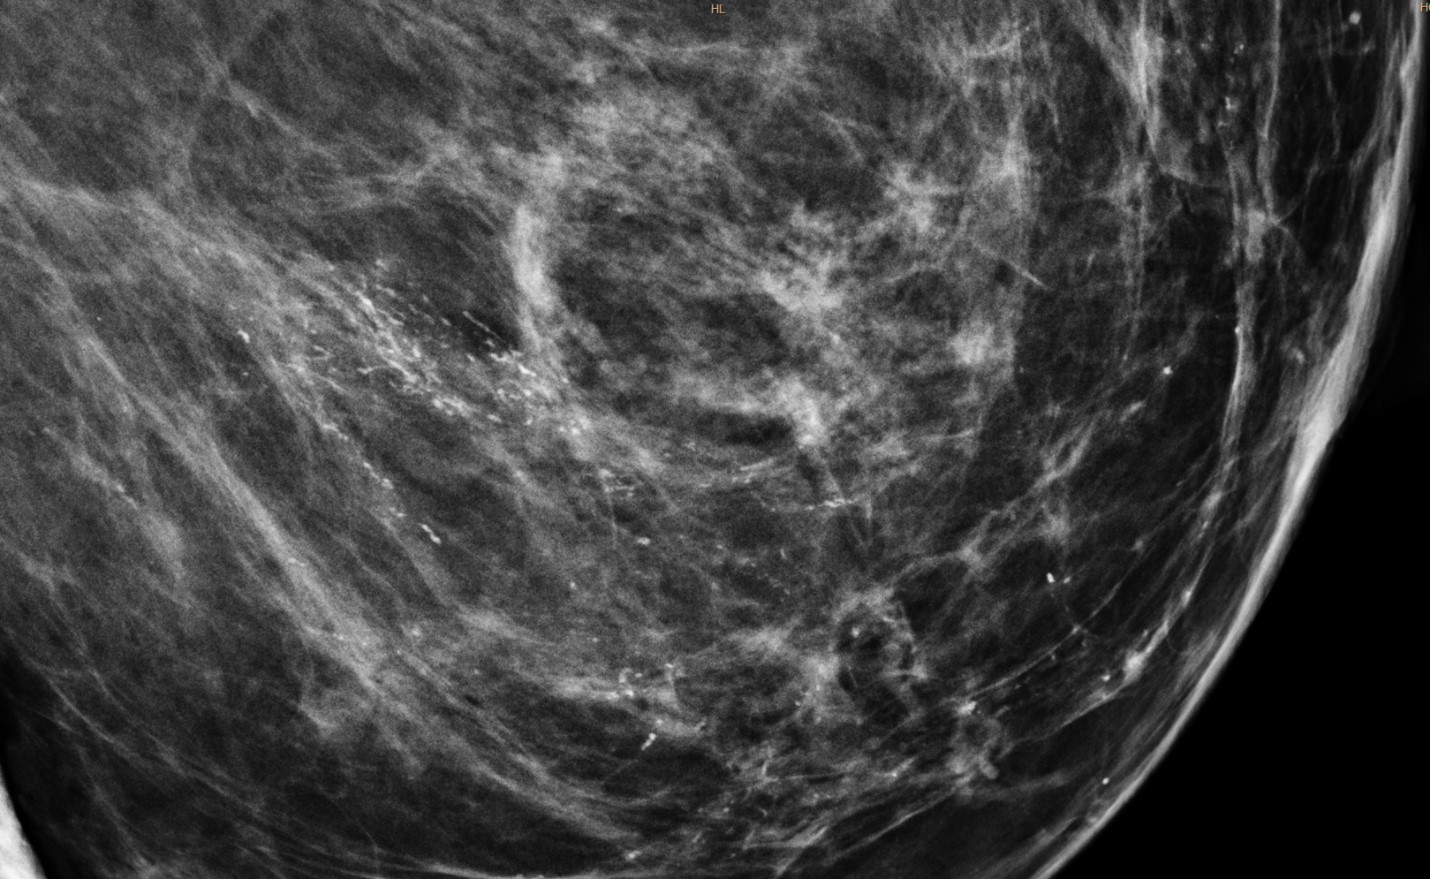

- Chụp X-quang vú (mammography): là phương pháp dùng một lượng tia X nhỏ để ghi lại hình ảnh của tuyến vú nhằm phát hiện những bất thường hoặc những khối u vú, đặc biệt là các vi vôi hóa khi chưa sờ thấy u qua thăm khám.

Hình minh họa: tổn thương vi vôi hóa ở vú phát hiện khi chụp X-quang

(Nguồn: commons.wikipedia.org)